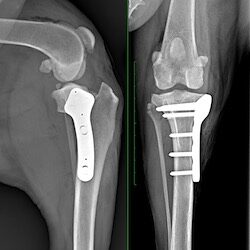

TPLO

TPLO is considered the gold standard for managing cranial cruciate ligament tears in dogs. Yielding better outcomes with fewer complications, it is the most reliable & predictable surgery available and is recommended by most orthopaedic surgeons.